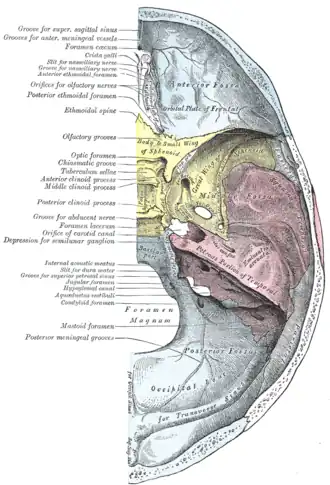

Base of the skull. Upper surface. (Condyloid canal not labeled, the occipital bone is visible at the bottom in blue, and the condyloid foramen is labeled at left, third from the bottom.) | |